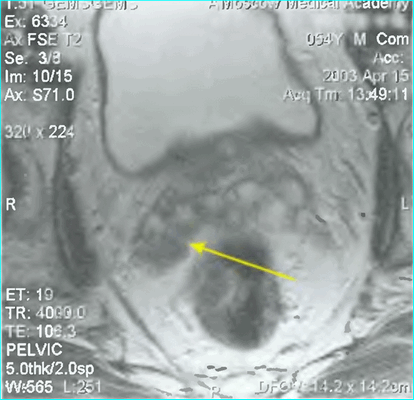

Пациент К., 1965 года рождения, при плановом обследовании в поликлинике по месту жительства в марте 2017 г. выявлено повышение уровня ПСА до 6,5 нг/мл, в связи с чем в ГКБ № 29 Москвы выполнена трансректальная биопсия предстательной железы, гистологически верифицирована ацинарная аденокарцинома 6 (3+3) баллов по Глисону. Больной самостоятельно обратился в МНИОИ им. П.А. Герцена. При пересмотре стекол препаратов биопсии предстательной железы в условиях патоморфологического отделения МНИОИ им. П.А. Герцена на фоне гиперплазии предстательной железы с очагами атрофии в 5 фрагментах из 12 выявлен рост ацинарной аденокарциномы 7 (4+3) баллов по Глисону, занимающей до 100% площади столбиков. По данным УЗИ и МРТ малого таза, предстательная железа размером 42×34×30 мм, объемом до 30 см 3 (рис. 3). Рис. 3. Магнитно-резонансная томограмма малого таза.

В периферической зоне правой доли определяется очаг раннего накопления контрастного препарата 13×10 мм без инвазии в капсулу железы и семенные пузырьки. В полости малого таза измененные лимфатические узлы не выявлены. При пальцевом ректальном исследовании предстательная железа не увеличена в размере, не деформирована, эластической консистенции, без пальпируемых узловых образований, междолевая бороздка сглажена. Слизистая оболочка прямой кишки над железой подвижна. Другой очаговой опухолевой патологии при комплексном обследовании не выявлено. На основании обследования установлен клинический диагноз: рак предстательной железы I стадии сТ2аN0M0. Больной обсужден на консилиуме с участием хирурга, химиотерапевта, лучевого терапевта и онколога: учитывая размер, локализацию и распространенность опухолевого процесса, отсутствие отдаленных и регионарных метастазов, рекомендовано хирургическое лечение. 10.04.17 больному выполнено хирургическое лечение в объеме радикальной простатэктомии, расширенной тазовой лимаденэктомии. Послеоперационный период протекал гладко, без особенностей. При контрольном УЗИ органов малого таза и вен нижних конечностей от 17.04.17 в полости малого таза объемных образований не выявлено. Поверхностные и глубокие вены обеих конечностей проходимы, без тромбоза и флебита. По данным цистографии от 17.04.17, подтверждена герметичность везикоуретрального анастомоза, в связи с чем 19.04.17 уретральный катетер удален, восстановлено самостоятельное мочеиспускание. Проведены антибактериальная, инфузионная, симптоматическая терапия и профилактика тромбоэмболических осложнений с положительным эффектом. Послеоперационная рана зажила первичным натяжением.